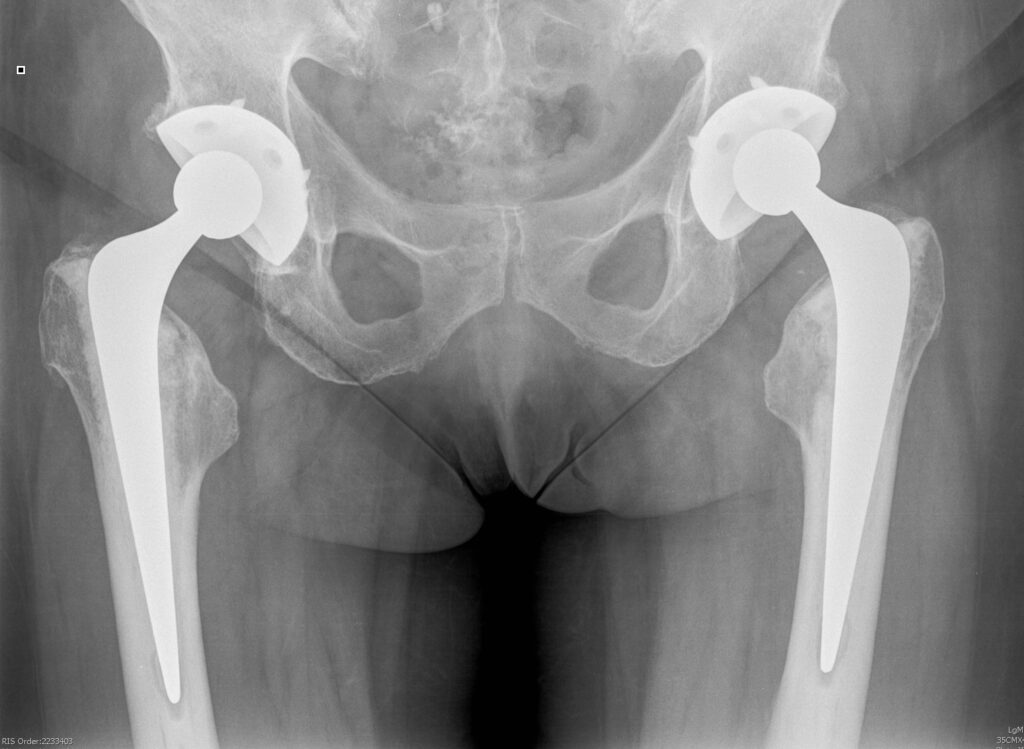

Below are the prostheses with links we commonly use but this is not exhaustive.